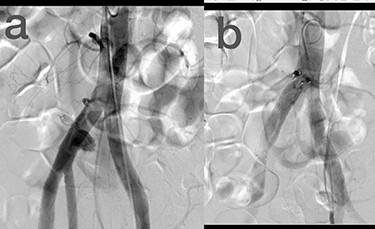

穿透性血管损伤的血管内治疗

Endovascular treatment of penetrating vascular injuries.

Endovascular treatment of vascular injuries has resulted in reduced operating time, blood loss, hospital mortality and sepsis. The purpose of this study was to evaluate the success and complication rate of the endovascular management of penetrating peripheral vascular injuries during 5 years. In this observational study, the clinical records and imaging features of 22 penetrating trauma injuries of 276 penetrating vascular trauma patients (8%), which were repaired using endovascular stent-grafts or coil embolization, between April 2013 and August 2018, included in the study. The median age of patients was 43 years (Range, 20-78 years). There were 17 stab wounds (77.3%), 2 shotgun war remnants (9.1%) and 2 iatrogenic post-surgical lesions. Eleven stent-grafts (50%) and nine coil embolizations (40.9%) were deployed. Endovascular interventions in the management of peripheral vascular injuries can be efficient in definitive repair, damage control and hemorrhage control in severely ill trauma patients.

血管损伤的血管内治疗已使手术时间、失血量、医院死亡率和败血症发生率降低。本研究的目的是评估5年间穿透性周围血管损伤的血管内治疗的成功率和并发症发生率。在这项观察性研究中,纳入了2013年4月至2018年8月期间276例穿透性血管创伤患者(8%)中22例穿透性创伤损伤的临床记录和影像特征,这些损伤采用血管内支架移植物或弹簧圈栓塞进行修复。患者的中位年龄为43岁(范围20 - 78岁)。有17处刺伤(77.3%)、2处散弹枪战争遗留伤(9.1%)和2处医源性术后损伤。使用了11个支架移植物(50%)和9次弹簧圈栓塞(40.9%)。血管内介入治疗周围血管损伤在危重伤员的确定性修复、损伤控制和出血控制方面可能是有效的。